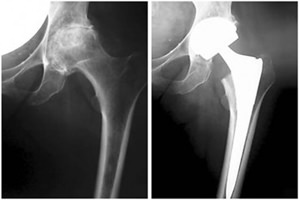

The company ORTHOPEDIC NIKIFOROV was founded in 1998 by the candidate of medical sciences. doctor of orthopedic-traumatologist of the highest category Nikiforov IA Owing to high professionalism and results of work, ORTONIC has gained well-deserved reputation and reputation among colleagues and population of Dnepropetrovsk region and CIS countries (Russia, Moldova, Armenia, etc.). The principle of the enterprise is NO IMPOSSIBLE, it is based on knowledge, experience and active implementation of modern technologies in orthopedics and traumatology. Conservative methods of treatment include individual selection of medicines, therapeutic blockades, manual therapy, massage, physiotherapy (vibration table, magnetotherapy, bioptron, electromyostimulation, etc.), rehabilitation with the suggestion of the necessary concomitant devices and means for the fastest recovery (corsets, bandages, various joint fixators, crutches, walking sticks, etc.). Various minor invasive interventions (chymonucleolysis, vertebroplasty, kyphoplasty, percutaneous nucleoplasty using cold plasma) that are performed on an outpatient basis are successfully used to treat problems associated with spine pathology. The latest modern treatment methods introduced in our company are endoscopic operations using the TYSSES technique of Joimax (Germany) with intervertebral hernias, stenosis and other pathologies of the spine, which allow to avoid complications occurring during open operations and the accompanying general anesthesia. We have many years of successful experience in traditional and modern minimally invasive endoprosthetics of large and small joints, which remains the main direction of our activity. Our company is the exclusive representative of the German company IO International Orthopaedics Holding GmbH, which based on the already known prostheses, its ideas and technological capabilities, has developed and implemented a new concept in hip replacement - an artificial joint prosthesis (ICON). We assist interested colleagues in training the operative technique for installing an artificial joint prosthesis - ICON, both in the workplace and in Germany. For 20 years we have been successfully cooperating with Sanitatshaus Gerd Klinz ortho team, an enterprise that for 20 years has been one of the leading places in Germany for the production of functional prostheses of the upper and lower limbs, as well as cosmetic prostheses of limbs and other body parts (nose, ears, eyeballs, fingers). We have an atmosphere of friendliness and human participation. Politeness, benevolence, the desire to understand and help is the basis of our attitude towards patients. We are always glad to see you and will do our best to make you feel great! We are waiting for you at: Ukraine, Dnepr, Gagarin Ave., 13 (under reconstruction) on all questions to address: tel .: +38 (050) 488-88-92 E-mail: orthonik.ukr@gmail.com Germany, Spine Nano Klinik, Zeppelinstr. 21, Potsdam Tel. +4901801121919 E-mail: kmw.nikiforov@hotmail.de